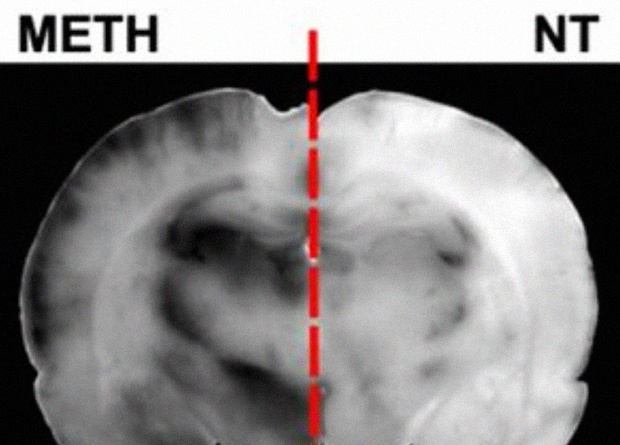

Один из предложенных способов «протаскивать» лекарства сквозь гематоэнцефалический барьер — при помощи метамфетамина. Это наркотическое вещество в концентрации более десяти микромоль на литр нарушает (иногда необратимо) плотные контакты между эндотелиальными клетками, и в барьере появляются бреши. В небольших же дозах метамфетамин тоже увеличивает проводимость гематоэнцефалического барьера, но не физически нарушая его, а усиливая везикулярный транспорт жидкостей сквозь клетки.

Ученые из Великобритании и Ирландии под руководством Патрика Туровски (Patric Turowski) из Университетского колледжа Лондона исследовали механизм воздействия метамфетамина на гематоэнцефалический барьер. Для этого создали модель